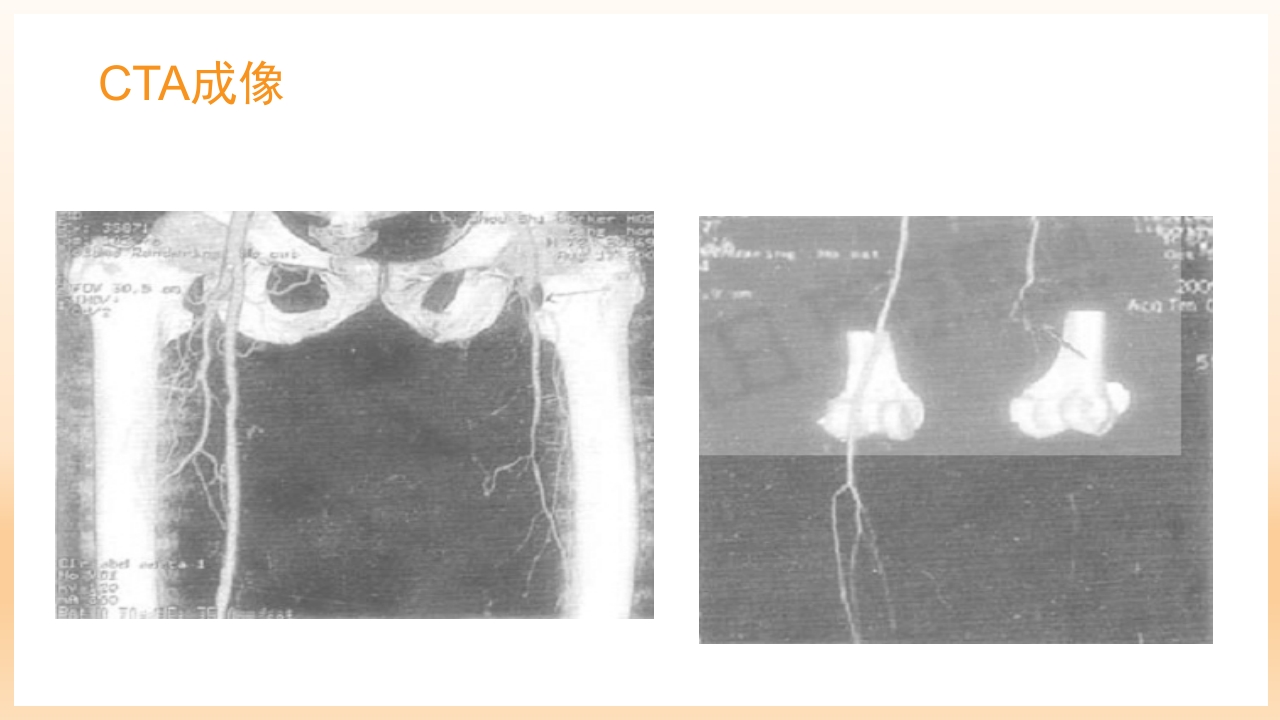

糖尿病足的治疗与护理 目录/content 一 糖尿病足的定义 二 糖尿病足发病机制及诊断? 三 糖尿病足如何治疗? 四 如何预防和护理糖尿尿足? 1 糖尿病足的定义 糖尿病足定义 糖尿病足:主要是与糖尿病下肢远端神经异常和不同程度的外 周血管病变相关的足部感染、溃疡和(或)深层组织破坏。 由于神经营养不良和外伤的共同作用,可引起Charot关节。 是糖尿病最严重的和治疗费用最高的慢性并发症之一。 糖尿病足流行病学资料 国外资料显示: 在所有因糖尿病住院的有关问题中,糖尿病足占到47%。 5%-10%糖尿病患者有不同程度足溃疡,1%的糖尿病患者截 肢。 糖尿病足是许多国家截肢首位原因。 中国糖尿病防治指南,2005,55 糖尿病足流行病学资料 在我国糖尿病足患病率占糖尿病患者的14%, ...